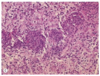

Glioblastoma multiforme, WHO grade IV, with prominent microvascular proliferation

Astrocytoma

- What kind is shown?

Glioblastoma multiforme, WHO grade IV, with significant nuclear pleomorphism and hyperchromaticity and a central focus of tumor cell necrosis